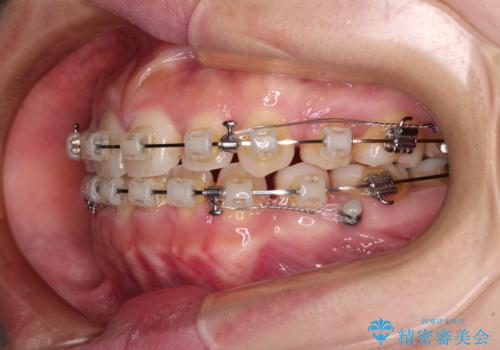

- クリアブラケット

上下ともに顎が小さく、歯列が前方に突き出していたため、上下左右の第一小臼歯4本を抜歯し、口元の突出感を改善していくこととしました。